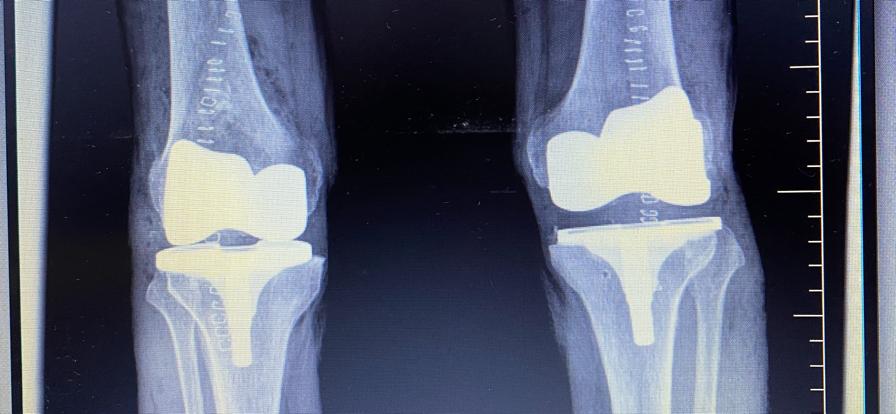

Recambio Articular de Rodilla con Prótesis de Rescate Medacta